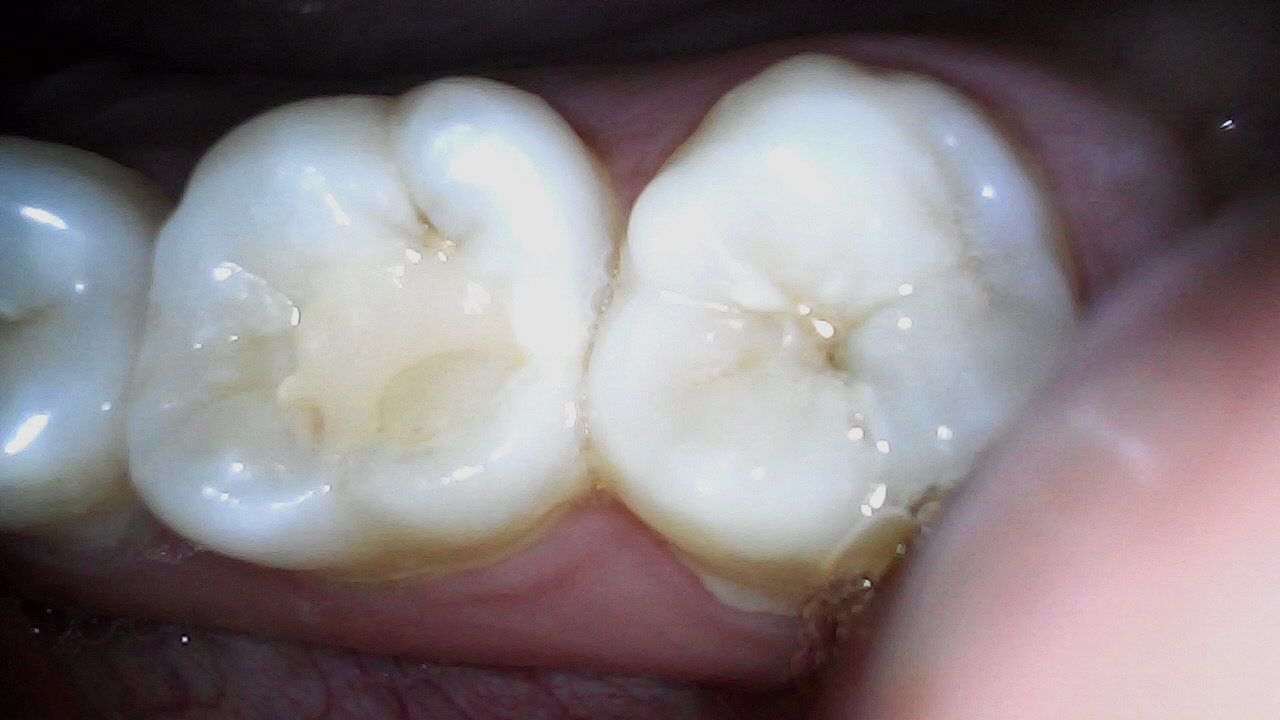

Final